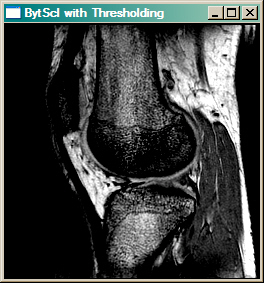

For example, the image below on the left is displayed with just the BytScl command, like this.

IDL> cgImage, BytScl(knee)

Whereas the image on the right uses a minimum threshold value of 1080 and a maximum threshold value of 1200.

IDL> cgImage, BytScl(knee, MIN=1080, MAX=1200)

When thresholding, all values in the image below the minimum threshold value are set to the threshold value before linear scaling occurs. Similarly, all values in the image greater than the maximum threshold value are set to the maximum threshold value before scaling. Notice the difference in contrast in the resulting image.

| The image on the left is byte scaled. The image on the right is byte scaled with a minumum threshold of 1080 and a maximum threshold of 1200. |